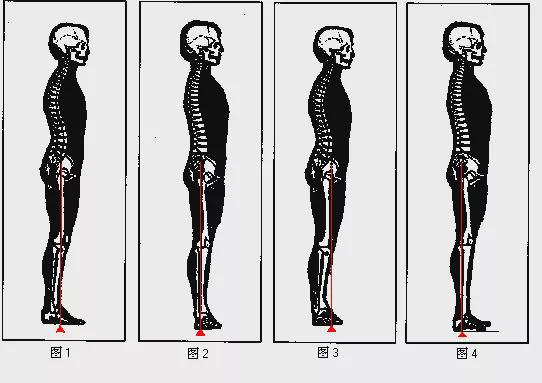

膝关节过伸又称膝关节过伸,英文为Hyperextend knee。人体膝关节正常的膝关节伸展范围是直到你能完全伸直你的膝盖,即你的大腿和小腿在一条直线上。如果在此基础上还能继续伸展膝盖,说明膝关节伸展过度了。 。站立时,如果膝关节达到过伸的位置,从侧面看,大腿和小腿会形成向后的弧线,所以有人把膝盖的过伸称为膝弓。

表现为站立或行走时双腿向后弹出,人的重心明显向后倾斜。这是导致步态异常的原因之一。

有两种简单的目测方法可以用来判断你是否在“正常屈伸范围”之外(判断膝关节过伸)

1、站立时,大腿和小腿之间的角度超过180度,形成“C”形(从正面看)。

2、小腿肚的位置远远落后于脚后跟(不包括那些肌肉异常发达的!!)。